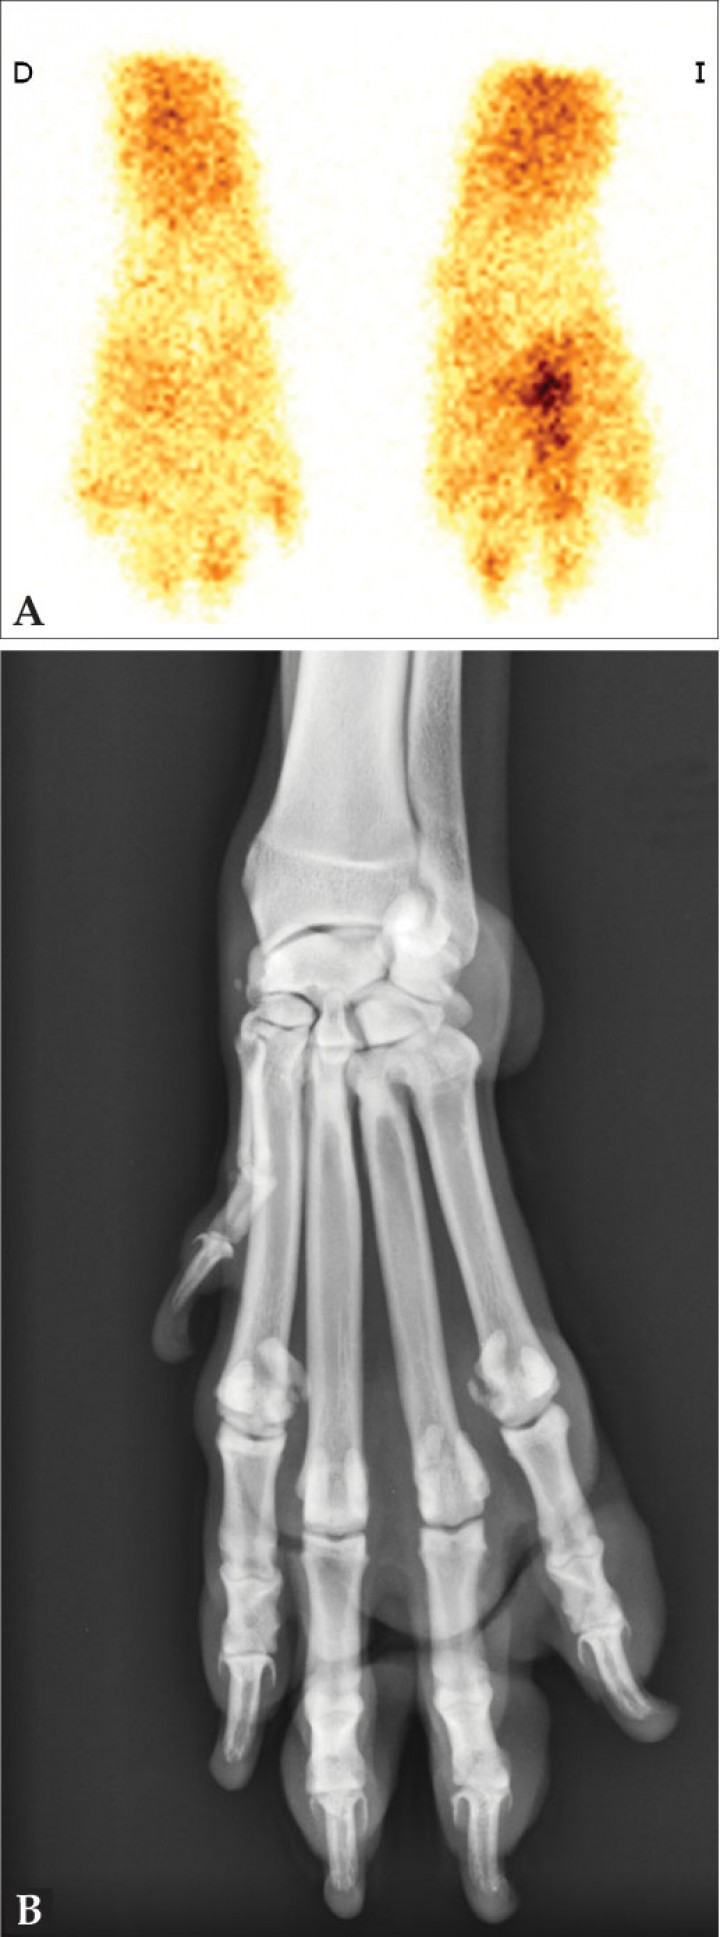

Ocasionalmente, el examen clínico puede no ser concluyente en la localización de la cojera debido a que el paciente presente una gran tolerancia al dolor, ausencia de palpación de anomalías morfológicas o no permita el examen por estrés, agresividad o hiperestesia.[ Schwarz T, Johnson VS, Voute L, Sullivan M. Bone scintigraphy in the investigation of occult lameness in the dog. J Small Anim Pract. 2004; 45(5):232-237. [PubMed] , Samoy Y, Van Ryssen B, Van Caelenberg A et al. Single-phase bone scintigraphy in dogs with obscure lameness. J Small Anim Pract. 2008; 49(9):444-450. [PubMed] ] La radiología puede así mismo no ser concluyente, ya que los cambios radiológicos pueden retrasarse en su aparición o no reflejar la causa de la cojera. La gammagrafía es una técnica muy sensible para detectar cambios tempranos en la remodelación ósea y/o verdadera patología y para evaluar la actividad de la lesión.[ Schwarz T, Johnson VS, Voute L, Sullivan M. Bone scintigraphy in the investigation of occult lameness in the dog. J Small Anim Pract. 2004; 45(5):232-237. [PubMed] , Samoy Y, Van Ryssen B, Van Caelenberg A et al. Single-phase bone scintigraphy in dogs with obscure lameness. J Small Anim Pract. 2008; 49(9):444-450. [PubMed] ] Por ejemplo, en el diagnóstico diferencial de cojeras del miembro anterior permite determinar si la patología tiene su origen en el codo (fragmentación del proceso coronoides medial) o en el hombro (lesiones del sistema extensor o contracturas del músculo infraespinoso/supraespinoso). Al localizar anatómicamente la lesión, es posible restringir a la zona afectada los estudios de tomografía computarizada (TC) o artroscopia (Figs. 11-13).[ Samoy Y, Van Ryssen B, Van Caelenberg A et al. Single-phase bone scintigraphy in dogs with obscure lameness. J Small Anim Pract. 2008; 49(9):444-450. [PubMed] , Van Bruggen LW, Hazewinkel HA, Wolschrijn CF, Voorhout G, Pollak YW, Barthez PY. Bone scintigraphy for the diagnosis of an abnormal medial coronoid process in dogs. Vet Radiol Ultrasound. 2010; 51(3):344-348. [PubMed] , Debruyn K, Peremans K, Vandermeulen E, Van Ryssen B, Saunders JH. Evaluation of semi-quantitative bone scintigraphy in canine elbows. Vet J. 2013; 196(3):424-430. [PubMed] ]

<p>Estudio por imagen de un perro con cojera oculta. (<strong>A</strong>) Gammagrafía en fase ósea en la que se observa un aumento de captación focal en el borde distal del IV metacarpiano de la mano izquierda. (<strong>B</strong>) Radiografía dorsopalmar de la articulación metacarpofalángica izquierda con signos de artrosis a la altura del cuarto metacarpiano y con sesamoideos metacarpofalángicos multipartidos. La gammagrafía permitió localizar el foco con patología en la porción distal de la extremidad, centrando el estudio radiológico en ella y sugiriendo la presencia de artrosis y tendinitis del flexor digital profundo.</p>

Figura 13

Estudio por imagen de un perro con cojera oculta. (A) Gammagrafía en fase ósea en la que se observa un aumento de captación focal en el borde distal del IV metacarpiano de la mano izquierda. (B) Radiografía dorsopalmar de la articulación metacarpofalángica izquierda con signos de artrosis a la altura del cuarto metacarpiano y con sesamoideos metacarpofalángicos multipartidos. La gammagrafía permitió localizar el foco con patología en la porción distal de la extremidad, centrando el estudio radiológico en ella y sugiriendo la presencia de artrosis y tendinitis del flexor digital profundo.